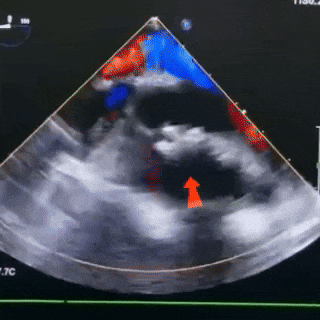

释放后观察

封堵器形态稳固

无残余分流,封堵成功